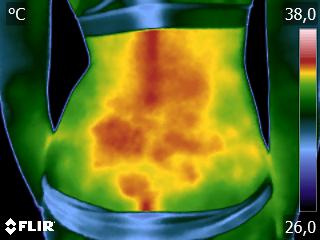

Como na sequência de termogramas abaixo de um paciente do sexo masculino, de 44 anos, sem comorbidades e praticante de atividade física que apresentou fortes dores em braço esquerdo (com irradiação para antebraço) após treino de musculação. Esta dor chegou a ser incapacitante, pois impossibilitava inclusive o paciente a realizar atividades de vida diárias como pegar um copo de água.

Após a realização de uma Análise Termofuncional©®, foi detectado alterações térmicas em “linha”, margeando as fibras musculares e tendíneas inferiores (insercionais) bicipitais. Estas alterações também aventaram a hipótese de dilatação venosa, por alguma reação inflamatória local. Foi realizado então aplicação de laserterapia através da Técnica Termoguiada, que acabou por promover a completa analgesia em 24 horas após aplicação.